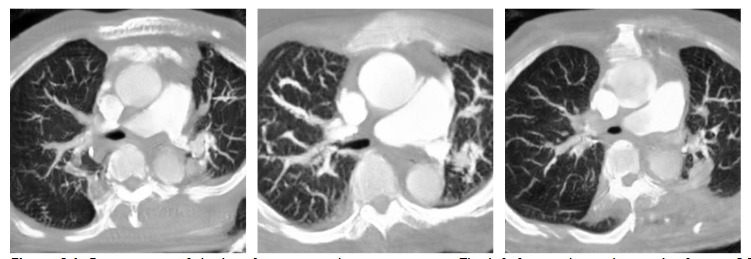

In previous research of our laboratory, it demonstrates that the deep learning model with hierarchical architecture can successfully distinguish CT scans with PE lesions and achieve high accuracy without using CTPA images, and indicates there are critical features on CT images for detecting PE. Previous proposed framework works in multiple stages on 3D lung CT scan images to detect and determine the malignancy of the nodules and also get the better result. That means CT scans have enormous potential for CT to CTPA translation. Much of the recent research employing deep learning methods for image-to-image translation has yielded significant improvements, aligning with the current trends in the field. For example, in medical imaging, the translation of images from Magnetic Resonance (MR) to Computed Tomography (CT) stands as a notable application of deep learning for medical image synthesis and continues to be one of the most frequently published topics in this domain. Since the main difference between CTPA image and CT image is the characteristic of the contrast agent, and both have similar cross-section shown in

, we can regard CT to CTPA translation as an image style conversion task.